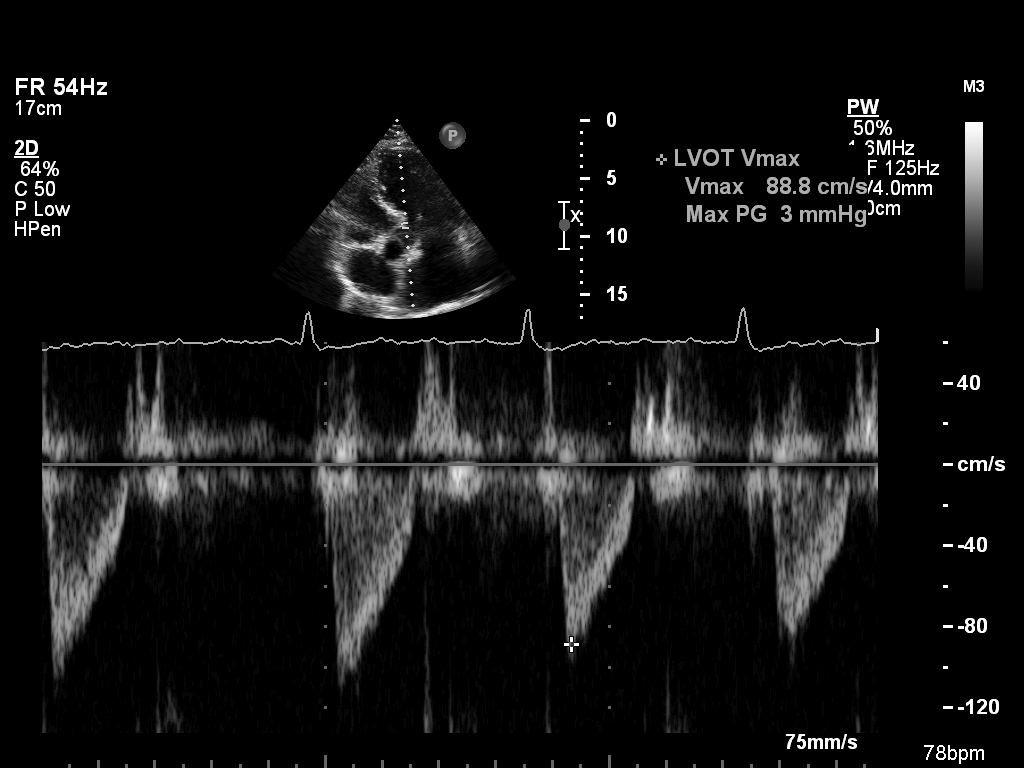

doppler-ao doppler-ao Spectral Doppler of the descending aorta

doppler-av doppler-av Spectral Doppler of the aortic valve